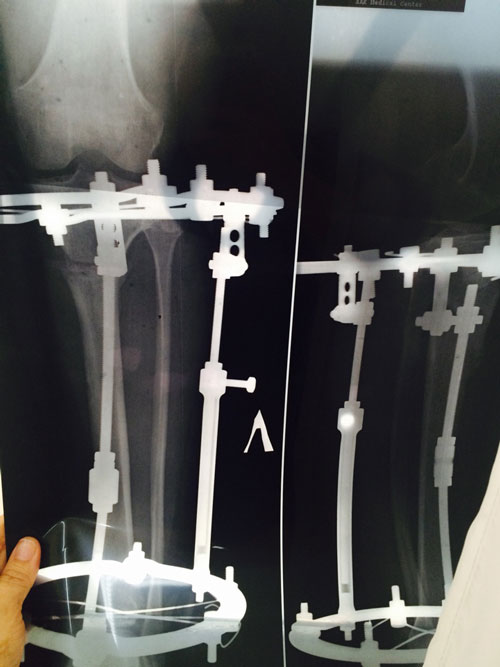

Диагноз: ахондроплазия, варусная деформация обеих голеней 155 градусов.

Дата операции 08.07.2015г.

Исходник.